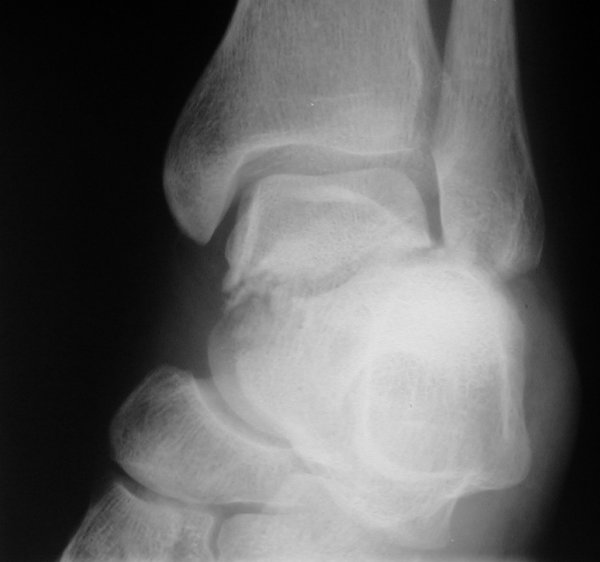

Return to Aviator's Astragalus